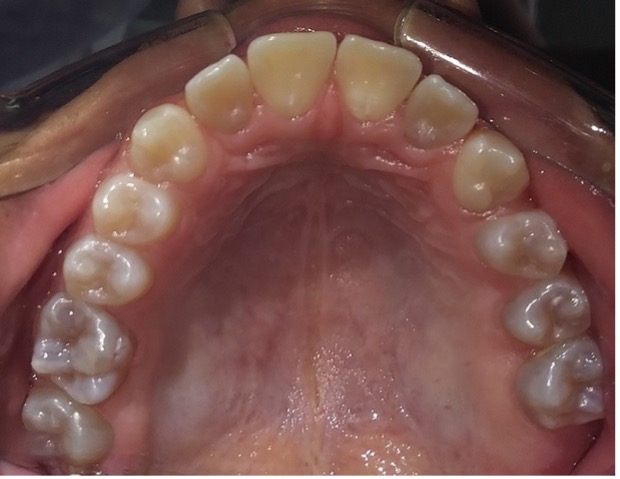

En el último control realizado en el año 2018 (Figura 11) el paciente mantuvo el estado de salud logrado. El análisis cariogénico fue moderado (por su historia pasada de caries y su condición biológica específica) y el gingivoperiodontal bajo. El paciente continúa en atención en la COIN. Fue derivado en varias oportunidades al servicio de Ortodoncia de la Facultad de Odontología de la Universidad de Buenos Aires, pero hasta el momento no encaró ningún tratamiento propuesto.

Figura 11: Controles clínicos 2018